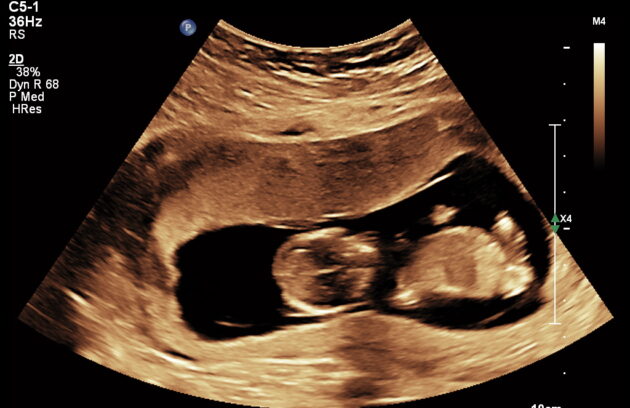

🔹 Anomaly Scan (Level II Ultrasound)

Anomaly Scan is a detailed ultrasound performed during pregnancy (usually between 18 and 22 weeks) to check the baby’s development. It helps detect structural abnormalities in the brain, heart, spine, kidneys, and other organs. This scan ensures your baby is growing normally and helps doctors identify any potential complications early. If you are looking for a reliable anomaly scan in Kathmandu, an early and accurate diagnosis is essential for a safe pregnancy.